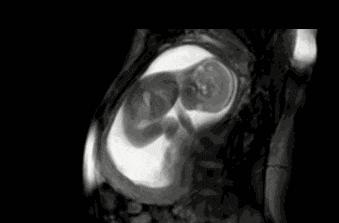

第9張圖:睡覺

媽媽數胎動時,有時一小時都安靜無聲,那是因爲寶寶正在睡覺。其實他們大部分時間都在睡覺,畢竟不用自己喫飯、呼吸,睡覺纔是長得最快的時候。